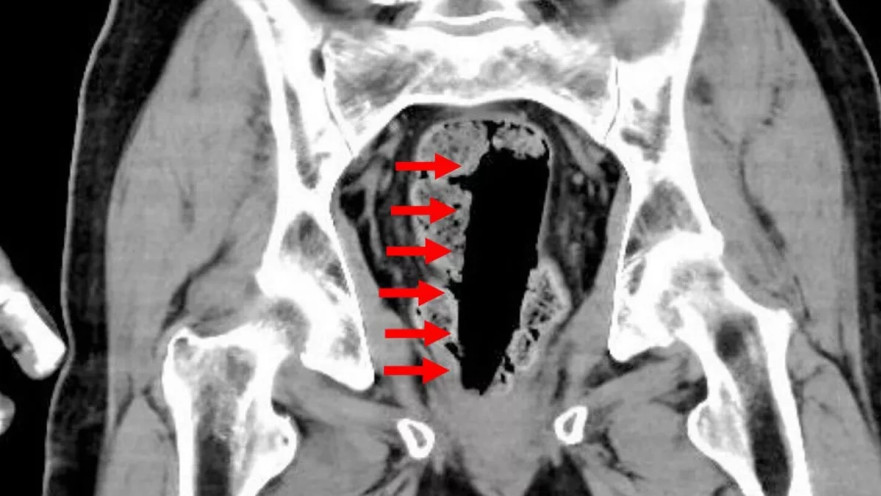

הרופאים שטיפלו במקרה החריג סיפרו כי הגבר, שסובל ממחלת פרקינסון, החדיר לעצמו מכל דבק בצורת חרוט, שאליו חובר חוט - כדי שיוכל לשלוף אותו בעצמו לאחר מכן. עם זאת, מצבו הידרדר, מה שהוביל לפינויו הדחוף לבית חולים בטוקיו. בדיקת CT שבוצעה לו במחלקה לרפואה דחופה וטיפול נמרץ בבית החולים Juntendo University Nerima העלתה כי מכל הדבק, בגודל של כ־35×35×120 מ״מ, נמצא בתוך גופו. הרופאים הצליחו להסיר את המכל באמצעות משיכה של החוט שחובר אליו, ללא צורך בניתוח.